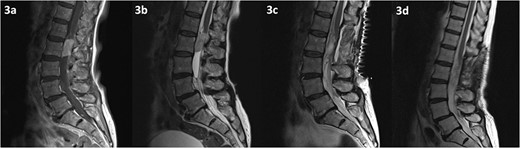

MRI of the spine revealed a 29 × 13 mm intradural soft tissue lesion at the level of L2, just below the conus (Fig. 3). The mass exhibited homogenous enhancement upon the administration of gadolinium. These non-specific specific findings lead to diagnostic uncertainty regarding the nature of the lesion. Nonetheless, there is an urgent need to halt or reverse the ongoing neurological deterioration.

MRI of the spine depicting an intradural lesion at the level of L2, just below the conus. The lesion demonstrates homogenous enhancement on contrast enhanced T1-weighted imaging (a). The lesion is hyperintense on T2-weighted imaging (b). There is no evidence of residual tumour on T2 weighted imaging at 2 days (c) and 14 months (d) postoperatively.